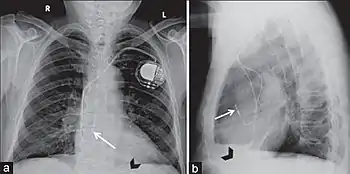

Insertion

A pacemaker may be implanted whilst a person is awake using local anesthetic to numb the skin with or without sedation, or asleep using a general anesthetic.[25] An antibiotic is usually given to reduce the risk of infection.[25] Pacemakers are generally implanted in the front of the chest in the region of the left or right shoulder. The skin is prepared by clipping or shaving any hair over the implant site before cleaning the skin with a disinfectant such as chlorhexidine. An incision is made below the collar bone and a space or pocket is created under the skin to house the pacemaker generator. This pocket is usually created just above the pectoralis major muscle (prepectoral), but in some cases the device may be inserted beneath the muscle (submuscular).[26] The lead or leads are fed into the heart through a large vein guided by X-ray imaging (fluoroscopy). The tips of the leads may be positioned within the right ventricle, the right atrium, or the coronary sinus, depending on the type of pacemaker required.[25] Surgery is typically completed within 30 to 90 minutes. Following implantation, the surgical wound should be kept clean and dry until it has healed. Some movements of the shoulder within a few weeks of insertion carry a risk of dislodging the pacemaker leads.[25]